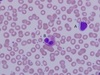

cardiac muscle